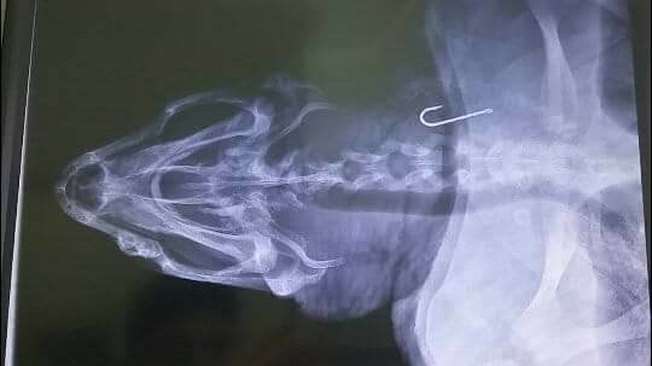

Caretta Caretta'nın röntgeninde balıkçı kancası

Vücudunun birçok noktasında çarpmaya bağlı yaralar bulunan deniz kaplumbağasının çekilen röntgenlerinde ise balıkçı kancası tespit edildi.

Kaplumbağayı yaşatmak için tedavinin sürdüğü öğrenildi. Kaplumbağanın çekilen röntgenlerinde balıkçı kancası tespit edildi.